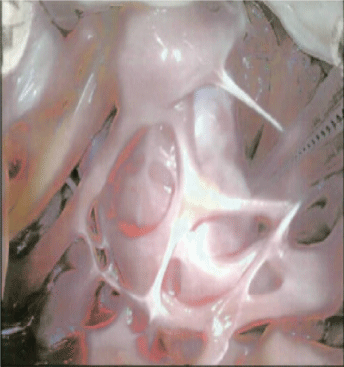

Diagnostic work up in the emergency department revealed normal complete blood count and blood chemistry profile. High-sensitivity troponin was elevated at 829 ng/L. BNP was normal at 30 pg/ml. Electrocardiogram (EKG) revealed a normal sinus rhythm at rate 63, left ventricular hypertrophy, left axis deviation of the QRS complex, which is unchanged from her baseline EKG. Due to a high suspicion of an acute venous thromboembolic phenomenon, ultrasound venous duplex of bilateral lower extremities was performed that revealed a near-occlusive acute deep vein thrombosis (DVT) of the right popliteal, posterior tibial and peroneal veins. Urgent CT-angiogram of the chest revealed a large saddle pulmonary embolus (PE) beginning at the distal main pulmonary artery and extending into the right and left pulmonary arteries.Distal propagation of the thrombus on the right side into the 1st and 2nd order branches supplying the right upper lobe, right lower lobe, and right middle lobe was noted.Additional findings of a deviated interventricular septum towards the left, suggesting mild right heart strain were observed.A 1.9 cm low density mass within the right ventricle (RV) was noted which was suspicious of a thrombus in transit. An urgent transthoracic echocardiogram (TTE) was performed to further evaluate the RV mass which revealed a normal left ventricular ejection fraction of 60%, moderately dilated RV with a normal systolic function, moderate tricuspid regurgitation, and a 2.4 cm X 1.9 cm circular density in the RV apex that appeared as a filling defect with echo contrast administration (Figure 1). Abnormal flattening of the interventricular septum during systole was also noted that was consistent with RV pressure overload. Pulmonary artery systolic pressure was mildly elevated at 46 mm Hg. Bubble study during the TTE also revealed a right to left intra-cardiac shunt via the interatrial septum.

Figure 1.Four chamber TTE image showing right ventricular apical mass